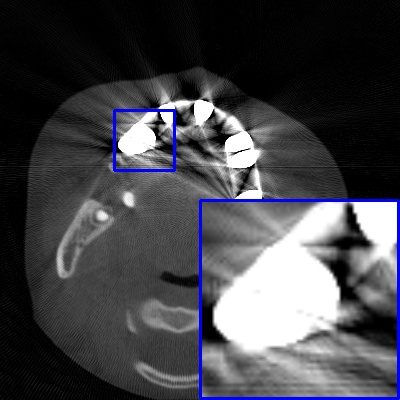

Figure 3: Visual comparison of MAR images by different methods on synthetic MA image. The PSNR (dB)/SSIM results are reported below each image for reference.

Results on synthetic MAR. In Table 1, we provide the quantitative results. One can see that our MARformer-L outperforms the other methods in terms of PSNR and SSIM, but needs only 11.76M parameters and 60.25G FLOPs. Note that the second best method Uformer-B has 50.42M parameters and 205.82G FLOPs. Besides, our MARformer-T achieves similar PSNR and SSIM results with Uformer-T, but needs only 0.40M parameters and 12.82G FLOPs compared to 5.24M and 25.39G for Uformer-T. Our MARformers also achieves faster inference speeds than the Uformers, though with inferior Dice scores, respectively. The qualitative results of visual quality are presented in Fig. 3. We observe that our MARformer-L well recovers the teeth shapes and obtains higher PSNR and SSIM results than the other comparison methods. The light-weight MARformer-L achieves similar results to Uformer-T. All these results validate that our MARformer is more efficient than the comparison methods on dental CBCT MAR.